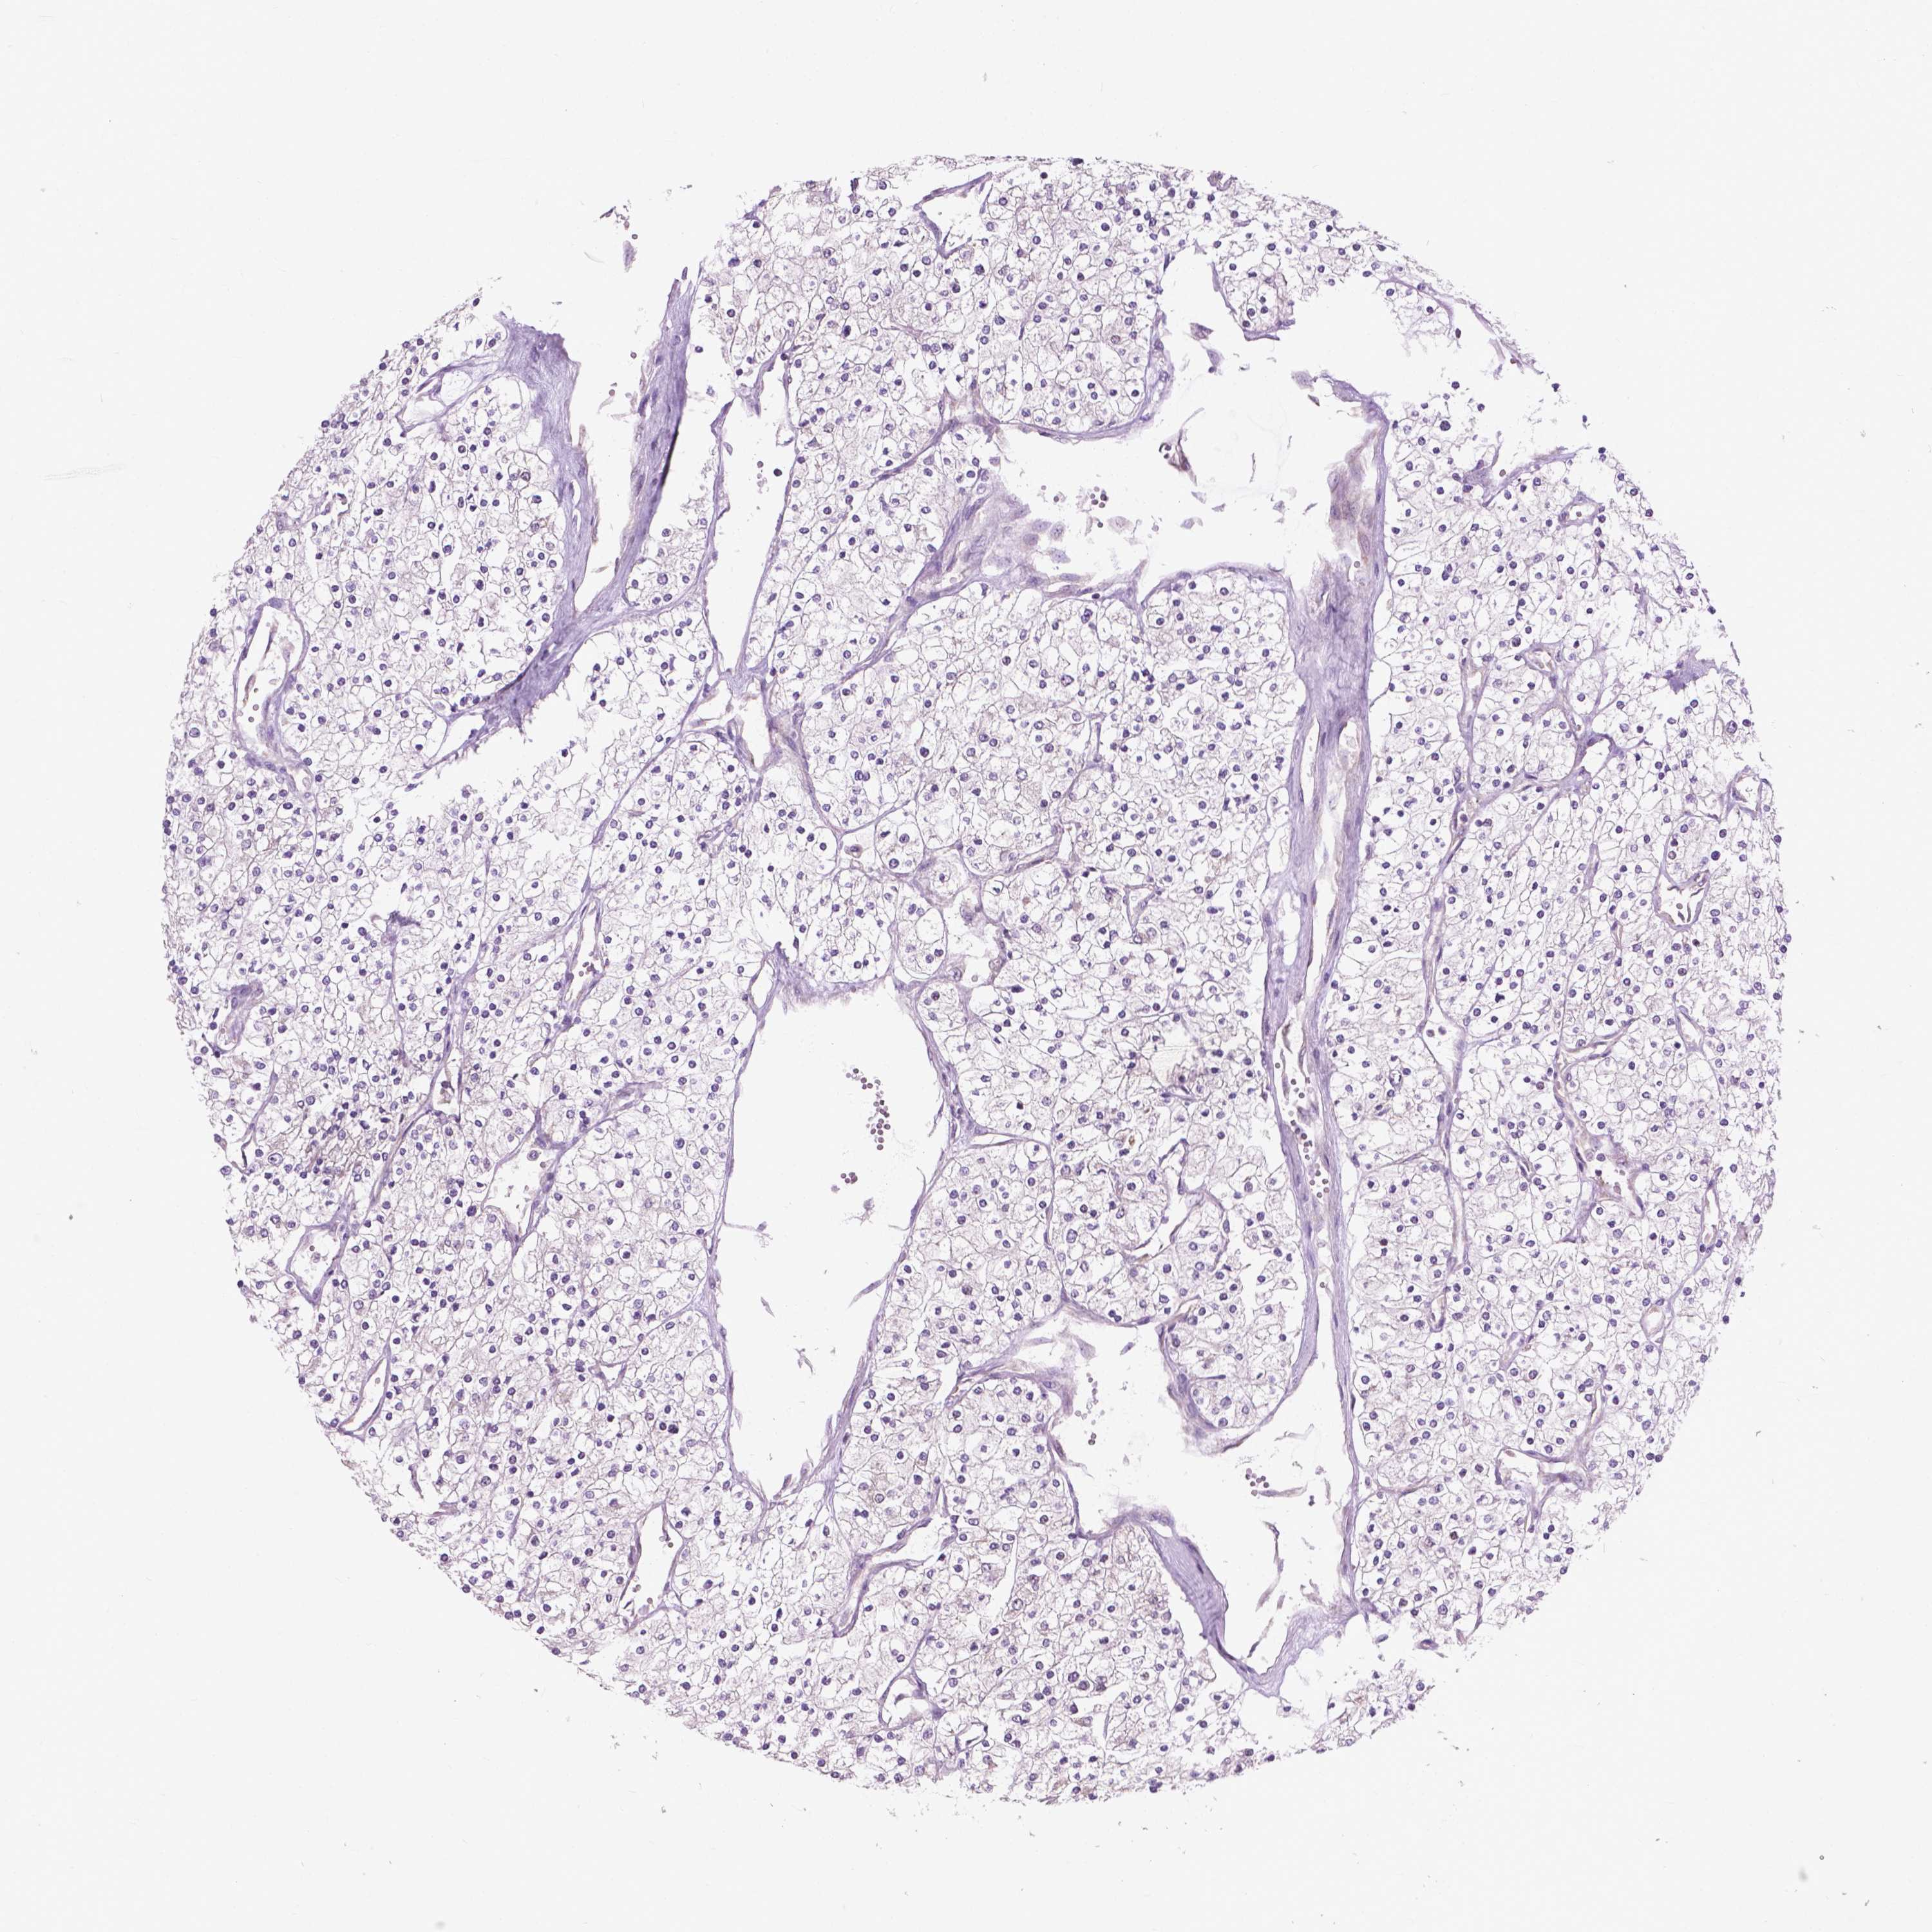

KIDNEY RENAL CLEAR CELL CARCINOMA (VALIDATION) - Interactive survival scatter ploti

The Survival Scatter plot shows the clinical status (i.e. dead or alive) for all individuals in the patient cohort, based on the same data that underlies the corresponding Kaplan-Meier plots. Patients that are alive at last time for follow-up are shown in blue and patients who have died during the study are shown in red.

The x-axis shows the expression levels (FPKM) of the investigated gene in the tumor tissue at the time of diagnosis. The y-axis shows the follow-up time after diagnosis (years). Both axes are complimented with kernel density curves demonstrating the data density over the axes. The top density plot shows the expression levels (FPKM) distribution among dead (red) and alive patients (blue). The right density plot shows the data density of the survived years of dead patients with high and low expression levels respectively, stratified using the cutoff indicated by the vertical dashed line through the Survival Scatter plot. This cutoff is automatically defined based on the FPKM cutoff that minimizes the p-score. The cutoff can be changed by dragging the vertical line or by entering a cutoff value in the square labeled "Current cut-off".

Under the Survival Scatter plot the p-score landscape (black curve; left axis) is shown together with dead median separation (red curve; right axis). Dead median separation is the difference in median mRNA expression between patients who have died with high and low expression, respectively. It is calculated as follows: median FPKM expression of dead patients with high expression - median FPKM expression of dead patients with low expression. This is intended to aid the user in visually exploring custom cutoffs and the associated p-scores and dead median separation.

Individual patient data is displayed and can be filtered by clicking on one or more of the category buttons on the top of the page. Categories describing expression level and patient information include: high, low, alive, dead, female, male and tumor stages. The scale of the x-axis can be toggled between linear and log-scale by clicking on the "x log" button. Mouse-over function shows TCGA ID, patient information and mRNA expression (FPKM) for each patient.

& Survival analysisi

Kaplan-Meier plots summarize results from analysis of correlation between mRNA expression level and patient survival. Patients were divided based on level of expression into one of the two groups "low" (under cut off) or "high" (over cut off). X-axis shows time for survival (years) and y-axis shows the probability of survival, where 1.0 corresponds to 100 percent.

MZT1 is not prognostic in Kidney Renal Clear Cell Carcinoma (validation)

Best expression cut offi

Based on the FPKM value of each gene, patients were classified into two groups and association between prognosis (survival) and gene expression (FPKM) was examined. The best expression cut-off refers the FPKM value that yields maximal difference with regard to survival between the two groups at the lowest log-rank P-value. Best expression cut-off was selected based on survival analysis .

When clicking on this number, the vertical dashed line indicating cut-off, the interactive survival plot, and the Kaplan-Meier curve will be adjusted to show results based on the best expression cut-off.

: 16.22

P scorei

Log-rank P value for Kaplan-Meier plot showing results from analysis of correlation between mRNA expression level and patient survival.

N/A

TCGA RNA samplesi

RNA-seq data is reported as average FPKM (number Fragments Per Kilobase of exon per Million reads), generated by the The Cancer Genome Atlas (TCGA) .

Normal distribution across the dataset is visualized with box plots, shown as median and 25th and 75th percentiles. Points are displayed as outliers if they are above or below 1.5 times the interquartile range. FPKM values of the individual samples are presented next to the box plot.

Average pTPM 19.1

Number of samples 100